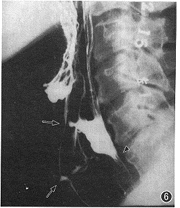

四、括约肌开闭

1.食管上括约肌(upper esophageal sphincter,UES):又称咽食管段或环咽部,由下咽缩肌及其远侧的食管环行肌组成,长2.5~4.0 cm。非吞咽时,UES处于闭合状态并保持约100 mm Hg(1 mm Hg=0.133 kPa)的高压。吞咽时,UES快速开放,持续0.2~0.3 s后关闭。开放的程度和时间因食(钡)团的大小、质地、到达的速度而不同。UES在EDR中常可清楚显示(图5)。除能直接观察其开放程度外,还可根据其近侧钡液滞留的数量和时间以及钡液进入气道(称aspiration,吸入)等情况,判断其开放的不适时和不适度性(图6),详见有关专著[9,13,14]。

图5 示UES开放(▲),钡剂正常通过时的表现。↑示舌骨位置

图6 UES(▲)功能紊乱,开放延迟,吞咽1次的钡剂不能1次完全通过,较多量钡剂在咽腔滞留,并有钡剂吸入气道(↑)

1.UES开闭功能不协调:在443例吞咽障碍病人中的出现率达19.5 %,主要与颅脑、颈部、食管等的病变及外伤有关[14](图6)。